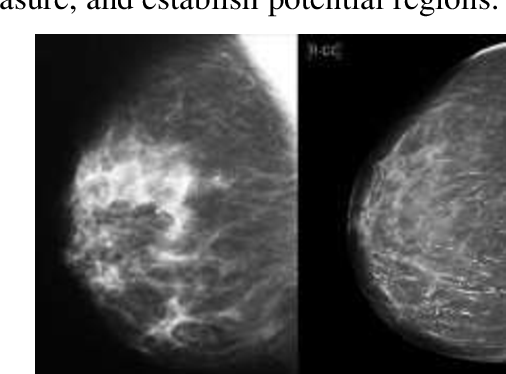

УЗИ молочных желез — информативный и безопасный метод диагностики, с помощью которого можно точно оценить состояние желез, обнаружить доброкачественные и злокачественные образования, уточнить диагноз. Это доступное по цене исследование безвредно и не несет лучевой нагрузки. Оно имеет большое значение в ранней диагностике заболеваний и нередко применяется в профилактических целях. На УЗИ может направить маммолог, онколог, эндокринолог, гинеколог.

Сделать УЗИ молочных желез можно в качестве первичной диагностики и для уточнения уже предполагаемого диагноза. Метод основывается на способности высокочастотных ультразвуковых волн с различной скоростью отражаться от тканей с разной плотностью.

С помощью ультразвуковой диагностики можно обнаружить следующие заболевания:

- воспалительные заболевания — мастит, абсцессы, лактостаз у кормящих женщин, мастопатии различного происхождения и типа — фиброзно-кистозные, диффузные и пр.;

- врожденные аномалии молочной железы;

- рак;

- кисты и доброкачественные опухоли;

Кому противопоказано

УЗИ практически не имеет противопоказаний. Однако важно отметить, что информативность обследования груди таким способом у женщин молодого возраста выше, поскольку ткани молочных желез с возрастом становятся более рыхлыми. Поэтому после 40 лет УЗИ в большинстве случаев сочетается с рентген-диагностикой (маммографией).